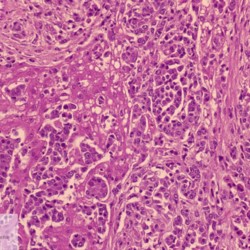

Etiquetes: N-738/00 1 total Canine Specie: Canine Organ: Liver Lesion: Carcinoma Lesion modifier: Carcinoma - Hepatocellular Disease: - Files/Expedient: N-738/00 Not viewed Títol Select...Avian (Exotic) (110)Avian (Poultry) (76)Bovine (317)Canine (935)Caprine (47)Equine (257)Feline (326)Ferret (19)General (127)Marine mammal (22)Non-human primate (20)Ovine (328)Porcine (379)Rabbit (61)Reptile (38)Rodent (28)Wildlife (91) Format Select...- (60)Abomasum (37)Adrenal gland (10)Blood (7)Blood vessel (50)Body as a whole (19)Bone (57)Bone marrow (21)Brain (93)Cloaca (1)Diaphragm (2)Ear (5)Esophagus (39)Eye (16)Fetus (12)Gallbladder (23)Gizzard (2)Heart (265)Intestine (356)Joint (32)Kidney (443)Larynx (5)Liver (326)Lung (264)Lymph node (91)Mammary gland (10)Mediastinum (1)Muscle (22)Nasal cavity (22)Nerve (7)Omasum (5)Oral cavity (63)Ovary (14)Oviduct (8)Pancreas (7)Parathyroid (5)Penis (10)Peritoneum (65)Pharynx (9)Pituitary gland (6)Placenta (7)Prostate (8)Proventriculus (3)Reticulum (1)Rumen (28)Sinus (7)Skin (181)Spinal cord (15)Spleen (105)Stomach (125)Teeth (1)Testicle (11)Thoracic cavity (31)Thymus (13)Thyroid gland (5)Tongue (32)Tonsils (11)Trachea (11)Urethra (5)Urinay bladder (61)Uterus (27)Vagina (1)Vulva (1)Yolk sac (1) Cobertura Select...- (152)Abomasitis (26)Abscess (27)Acidosis (1)Adenocarcinoma (20)Adenoma (9)Aerosacculitis (6)Agenesis (1)Agnathia (1)Alopecia (7)Amyloidosis (12)Aneurysm (6)Angiectasis (1)Anthracosis (1)Arteritis (11)Arthritis (15)Arthrogryposis (6)Artifact (4)Ascites (13)Atelectasis (8)Atherosclerosis (5)Atresia (1)Atrial septal defect (2)Atrophy (10)Autolysis (7)Bronchitis (6)Bronchopneumonia (26)Cachexia (2)Carcinoma (103)Cardiomyopathy (19)Cellulitis (2)Chemodectoma (4)Cholangiohepatitis (4)Cholangitis (19)Cholecystitis (4)Cholestasis (5)Chondrodysplasia (2)Chondrosarcoma (2)Chronic passive congestion (13)Chylothorax (2)Cirrhosis (6)Coelomitis (3)Coenurus cerebralis (4)Colitis (40)Congestion (17)Conjunctivitis (5)Coronitis (3)Cryptorchidism (3)Cyst (25)Cystitis (24)Dermatitis (69)Diaphragmatic hernia (4)Dilation (28)Discospondylitis (1)Disseminated intravascular coagulation (7)Dyschondroplasia (1)Dysplasia (29)Ectopia cordis (1)Ectopic ureter (1)Edema (55)Emphysema (5)Encephalitis (5)Endocardiosis (14)Endocarditis (26)Endometritis (5)Enteritis (118)Enterolith (6)Epulis (3)Esophagitis (14)Fasciitis (1)Fibrosis (7)Fibrous osteodystrophy (8)Fistula (1)Folliculitis (3)Fracture (2)Gastritis (34)Gingivitis (5)Glioma (8)Glomerulonephritis (21)Glossitis (25)Glycogenosis (1)Gout (8)Granuloma (2)Granulosa cell tumor (4)Hemangioma (9)Hemangiosarcoma (46)Hematoma (8)Hemoglobinuria (2)Hemopericardium (12)Hemoperitoneum (2)Hemorrhage (100)Hemosiderosis (7)Hemothorax (2)Hepatitis (78)Hernia (11)Histiocytosis (3)Hydatid cyst (11)Hydrocephalus (9)Hydrometra (1)Hydronephrosis (22)Hydropericardium (6)Hydrothorax (3)Hydroureter (5)Hyperkeratosis (8)Hyperostosis (4)Hyperplasia (37)Hypertrophy (9)Hypopigmentation (1)Hypoplasia (7)Hypopyon (1)Impaction (6)Infarction (63)Insulinoma (6)Intussusception (5)Jaundice (17)Laminitis (2)Laryngitis (2)Leiomyoma (5)Leukemia (13)Lipidosis (36)Lipoma (7)Lymphadenitis (45)Lymphadenopathy (7)Lymphangiectasia (6)Lymphangitis (5)Lymphoma (221)Malacia (11)Malignant melanoma (15)Mast cell tumor (11)Mastitis (8)Megaesophagus (2)Melanosis (3)Melena (4)Meningioma (6)Meningitis (6)Meningocele (2)Meningoencephalitis (5)Mesothelioma (5)Methemoglobinemia (2)Mineralization (10)Mucocele (5)Mucometra (1)Multilobular bone tumor (1)Mummification (3)Myelofibrosis (1)Myocarditis (4)Myositis (5)Necrosis (81)Nephritis (113)Nephroblastoma (6)Nephrosclerosis (1)Nephrosis (14)Neuritis (1)Obstruction (13)Omasitis (4)Omphalitis (1)Omphalophlebitis (7)Orchitis (4)Osteoarthrosis (5)Osteomyelitis (9)Otitis (2)Palatoschisis (3)Pancreatitis (3)Panniculitis (3)Papilloma (7)Parakeratosis (14)Patent ductus arteriosus (6)Peliosis hepatis (1)Perforation (17)Pericarditis (35)Peritonitis (39)Persistent right aortic arch (1)Pharyngitis (2)Pheochromocytoma (2)Phlebitis (2)Placentitis (6)Pleuritis (21)Pleuropneumonia (24)Pneumonia (109)Pneumothorax (3)Polycystosis (14)Polyp (5)Polyserositis (6)Posthitis (1)Proctitis (4)Prolapse (3)Prostatitis (3)Proventriculitis (1)Pyelonephritis (24)Pyometra (6)Pyothorax (4)Rhinitis (11)Rumenitis (6)Rupture (24)Salpingitis (3)Sarcoma (57)Sclerosis (1)Scoliosis (2)Seminoma (2)Sequestrum (2)Serous atrophy (14)Sinusitis (7)Splenitis (14)Splenomegaly (9)Spondylitis (6)Spondylosis (1)Stenosis (9)Stomatitis (32)Tenosynovitis (2)Teratoma (3)Thricobezoar (2)Thrombosis (16)Tonsilitis (4)Torsion (13)Tracheitis (4)Tympany (7)Typhlitis (8)Typhlocolitis (4)Ulcer (43)Urethritis (1)Urolithiasis (36)Uroperitoneum (1)Uveitis (1)Vasculitis (15)Ventricular septal defect (3)Volvulus (11) Matèria Select... - (14)- (1653)- (152)Abomasitis - Catarrhal (2)Abomasitis - Catarrhal-hemorrhagic (1)Abomasitis - Chronic (1)Abomasitis - Fibrinous-necrotizing (2)Abomasitis - Hyperplasic (5)Abomasitis - Hyperplasic - Chronic (1)Abomasitis - Necrotic (1)Abomasitis - Necrotizing (2)Abomasitis - Ulcerative (5)Adenocarcinoma (9)Aerosacculitis - Granulomatous (1)Amyloidosis - Chronic (1)Arteritis - Necrotic (2)Arteritis - Necrotizing (1)Arthritis - Chronic (4)Arthritis - Fibrinous-purulent (3)Arthritis - Serous (4)Arthritis - Subacute (1)Ascites - Serous (1)Atrophy - Serous (1)Bronchitis - Catarrhal (3)Bronchitis - Suppurative (1)Bronchopneumonia - Catarrhal-purulent (17)Bronchopneumonia - Fibrinous (1)Bronchopneumonia - Granulomatous (1)Bronchopneumonia - Purulent (1)Bronchopneumonia - Suppurative (5)Carcinoma - Adenocarcinoma (33)Carcinoma - Adenocarcinoma - Hepatocellular (2)Carcinoma - Adenocarcinoma - Mucinous (1)Carcinoma - Basosquamous (1)Carcinoma - Cholangiocellular (3)Carcinoma - Hepatocellular (4)Carcinoma - Metastatic (3)Carcinoma - Squamous cell carcinoma (13)Carcinoma - Transitional cell (2)Cardiomyopathy - Dilated (13)Cardiomyopathy - Hypertrophic (6)Cellulitis - Necrotizing (1)Cholangitis - Chronic (8)Cholangitis - Hyperplasic (3)Cholecystitis - Fibrinous-necrotizing (1)Coelomitis - Fibrinous (1)Coelomitis - Granulomatous (1)Colitis - Catarrhal (3)Colitis - Catarrhal-hemorrhagic (1)Colitis - Fibrinous (1)Colitis - Fibrinous-necrotizing (1)Colitis - Fibrinous-necrotizing (Diphtheritic) (6)Colitis - Granulomatous (2)Colitis - Hemorrhagic (4)Colitis - Hemorrhagic-necrotizing (3)Colitis - Necrotizing (2)Colitis - Ulcerative (6)Congestion - Chronic (2)Conjunctivitis - Hyperplasic (1)Conjunctivitis - Purulent (3)Coronitis - Ulcerative (1)Cystitis - Chronic (3)Cystitis - Fibrinous (1)Cystitis - Fibrinous-necrotizing (1)Cystitis - Follicular (1)Cystitis - Hemorrhagic (6)Cystitis - Hemorrhagic-ulcerative (1)Cystitis - Necrotizing (9)Cystitis - Perforated (1)Dermatitis - Granulomatous (14)Dermatitis - Hyperkeratotic (10)Dermatitis - Hyperplasic (proliferative) (1)Dermatitis - Hyperplastic (10)Dermatitis - Necrotizing (4)Dermatitis - Pustular (4)Dermatitis - Ulcerative (2)Dilation - Chronic (1)Discospondylitis - Necrotizing (1)Dysplasia - Follicular (5)Edema - Interstitial (6)Emphysema - Interstitial (1)Encephalitis - Granulomatous (1)Encephalitis - Nonsuppurative (1)Endocardiosis - Mitral (7)Endocardiosis - Mitral - Chronic (5)Endocarditis - Valvular (6)Endocarditis - Valvular - Mitral (7)Endocarditis - Valvular - Pulmonic (1)Endocarditis - Valvular - Subacute (1)Endocarditis - Valvular - Subaortic (5)Endocarditis - Valvular - Tricuspid (4)Endometritis - Purulent (3)Endometritis - Purulent-hemorrhagic (2)Enteritis - Catarrhal (23)Enteritis - Catarrhal - Acute (1)Enteritis - Catarrhal-hemorrhagic (5)Enteritis - Catarrhal-hemorrhagic - Acute (2)Enteritis - Fibrinous (16)Enteritis - Fibrinous - Acute (3)Enteritis - Fibrinous-necrotizing (7)Enteritis - Granulomatous (14)Enteritis - Granulomatous - Chronic (1)Enteritis - Granulomatous - Multifocal (1)Enteritis - Hemorrhagic (17)Enteritis - Hemorrhagic - Acute (1)Enteritis - Hemorrhagic-necrotizing (1)Enteritis - Hyperplasic (proliferative) (4)Enteritis - Necrotizing (4)Enteritis - Necrotizing - Acute (1)Enteritis - Necrotizing - Hemorrhagic (1)Enteritis - Necrotizing-ulcerative (2)Enteritis - Ulcerative (1)Enteritis - Ulcerative-hemorrhagic (1)Esophagitis - Erosive-ulcerative (6)Esophagitis - Necrotizing (4)Esophagitis - Ulcerative (1)Esophagitis - Ulcerative-necrotizing (1)Fasciitis - Fibrinous-purulent (1)Folliculitis - Purulent (2)Gastritis - Catarrhal (2)Gastritis - Chronic (1)Gastritis - Follicular (1)Gastritis - Hemorrhagic (2)Gastritis - Hemorrhagic-necrotizing (1)Gastritis - Hypertrophic (2)Gastritis - Inclusion bodies (1)Gastritis - Mineralization (1)Gastritis - Mycotic (1)Gastritis - Necrotizing (2)Gastritis - Ulcerative (6)Gastritis - Uremic (3)Gingivitis - Erosive (2)Gingivitis - Hyperplasic (proliferative) (1)Gingivitis - Necrotizing (1)Glomerulonephritis - Chronic (7)Glomerulonephritis - Membranoproliferative (3)Glomerulonephritis - Membranoproliferative - Chronic (1)Glomerulonephritis - Membranous (3)Glomerulonephritis - Membranous - Chronic (1)Glomerulonephritis - Proliferative (2)Glomerulonephritis - Subacute (1)Glossitis - Erosive (2)Glossitis - Granulomatous (6)Glossitis - Hyperplasic (1)Glossitis - Hyperplasic (proliferative) (2)Glossitis - Hyperplastic (1)Glossitis - Necrotizing (2)Glossitis - Necrotizing - Focal (1)Glossitis - Ulcerative (6)Glossitis - Ulcerative - Multifocal (1)Glossitis - Ulcerative - Subacute (1)Glycogenosis (1)Granuloma - Eosinophilic (1)Hemangiosarcoma - Metastatic (2)Hemorrhage - Acute (1)Hemorrhage - Subcapsular (3)Hepatitis - Abscess (9)Hepatitis - Acute (3)Hepatitis - Chronic (4)Hepatitis - Chronic interstitial (6)Hepatitis - Granulomatous (7)Hepatitis - Interstitial - Multifocal (1)Hepatitis - Interstitial - Subacute (1)Hepatitis - Necrotizing (17)Hepatitis - Necrotizing - Acute (2)Hepatitis - Necrotizing - Hemorrhagic (1)Hepatitis - Necrotizing - Subacute (1)Hepatitis - Pyogranulomatous (7)Hepatitis - Subacute (4)Hydronephrosis - Chronic (1)Hydropericardium - Chronic (1)Hyperplasia - Erythroid (1)Hyperplasia - Lymphoid (3)Hyperplasia - Myeloid (1)Hyperplasia - Nodular (8)Hypertrophy - Concentric (2)Hypertrophy - Eccentric (3)Infarction - Acute (17)Infarction - Acute - Multifocal (2)Infarction - Chronic (5)Infarction - Chronic - Multifocal (1)Infarction - Subacute (18)Infarction - Subacute - Focal (2)Laminitis - Chronic (2)Laryngitis - Necrotic (1)Laryngitis - Necrotizing (1)Leukemia - Lymphoid leukemia (2)Leukemia - Non-lymphoid leukemia (6)Lipidosis - Multifocal (1)Lipidosis - Panlobular (1)Lipidosis - Panlobular - Generalized (2)Lymphadenitis - Granulomatous (24)Lymphadenitis - Granulomatous - Chronic (3)Lymphadenitis - Hemorrhagic (1)Lymphadenitis - Necrotizing (5)Lymphadenitis - Necrotizing (caseous) (11)Lymphangitis - Granulomatous (1)Lymphangitis - Purulent (1)Lymphangitis - Ulcerative (1)Lymphoma - Alimentary lymphoma (7)Lymphoma - Cutaneous lymphoma (6)Lymphoma - Lymphosarcoma (2)Lymphoma - Mediastinal lymphoma (1)Lymphoma - Multicentric lymphoma (29)Malignant melanoma - Malignant (1)Malignant melanoma - Metastatic (1)Mast cell tumor - Metastatic (1)Mastitis - Fibrinous-purulent (2)Mastitis - Necrotic (1)Mastitis - Purulent (3)Mastitis - Suppurative (1)Meningitis - Fibrinous-purulent (2)Meningitis - Purulent (4)Meningoencephalitis - Necrotizing (3)Meningoencephalitis - Nonsuppurative (2)Mineralization - Metastatic (4)Myocarditis - Fibrous - Chronic (1)Myocarditis - Granulomatous (1)Myositis - Purulent (2)Necrosis - Acute (1)Necrosis - Cortical (5)Necrosis - Follicular (1)Necrosis - Papillary (8)Necrosis - Papillary - Acute (3)Necrosis - Subacute (3)Necrosis - Tubular (6)Nephritis - Embolic (2)Nephritis - Embolic suppurative (7)Nephritis - Granulomatous (27)Nephritis - Granulomatous - Chronic (1)Nephritis - Granulomatous - Multifocal (1)Nephritis - Interstitial (6)Nephritis - Interstitial - Acute (4)Nephritis - Interstitial - Chronic (41)Nephritis - Interstitial - Subacute (12)Nephritis - Purulent (7)Nephritis - Purulent - Acute (2)Nephritis - Purulent - Multifocal (3)Nephrosis - Cholemic (3)Nephrosis - Hemoglobinuric (10)Omasitis - Fibrinous-necrotizing (1)Omasitis - Hyperkeratotic (1)Omasitis - Necrotizing (2)Omphalophlebitis - Fibrinous-purulent (2)Omphalophlebitis - Purulent (3)Orchitis - Necrotizing (1)Osteomyelitis - Necrotizing (7)Osteomyelitis - Purulent (2)Otitis - Necrotizing (1)Otitis - Proliferative (1)Pancreatitis - Acute (1)Pancreatitis - Chronic (1)Pancreatitis - Granulomatous (1)Panniculitis - Fibrinous-purulent (1)Panniculitis - Necrotic (1)Panniculitis - Parasitic (1)Perforation - Acute (2)Pericarditis - Fibrinous (19)Pericarditis - Fibrinous - Subacute (1)Pericarditis - Fibrinous-necrotizing (1)Pericarditis - Fibrinous-purulent (3)Pericarditis - Fibrous (1)Pericarditis - Fibrous - Chronic (1)Pericarditis - Gangrenous (6)Pericarditis - Granulomatous (1)Pericarditis - Granulomatous - Chronic (2)Peritonitis - Acute (1)Peritonitis - Fibrinous (11)Peritonitis - Fibrinous - Subacute (1)Peritonitis - Fibrinous-purulent (5)Peritonitis - Fibrous (3)Peritonitis - Granulomatous (6)Peritonitis - Purulent (1)Peritonitis - Purulent-hemorrhagic (1)Peritonitis - Pyogranulomatous (3)Pharyngitis - Fibrinous-necrotizing (1)Pharyngitis - Ulcerative (1)Pheochromocytoma - Metastatic (1)Phlebitis - Purulent (1)Placentitis - Fibrinous-necrotizing (1)Placentitis - Necrotic (1)Placentitis - Necrotizing (1)Pleuritis - Chronic (1)Pleuritis - Fibrinous (3)Pleuritis - Fibrinous-purulent (2)Pleuritis - Fibrous (2)Pleuritis - Granulomatous (3)Pleuritis - Hyperplastic (2)Pleuritis - Purulent (2)Pleuritis - Pyogranulomatous (1)Pleuropneumonia - Fibrinous (13)Pleuropneumonia - Fibrinous-necrotizing (5)Pleuropneumonia - Granulomatous (2)Pleuropneumonia - Hemorrhagic-necrotizing (4)Pneumonia - Aspiration (11)Pneumonia - Bronchointerstitial (4)Pneumonia - Bronchointerstitial - Subacute (1)Pneumonia - Embolic (5)Pneumonia - Granulomatous (37)Pneumonia - Granulomatous - Multifocal (4)Pneumonia - Hemorrhagic-necrotizing (2)Pneumonia - Interstitial (7)Pneumonia - Interstitial - Acute (8)Pneumonia - Interstitial - Chronic (6)Pneumonia - Interstitial - Subacute (15)Pneumonia - Necrotizing (2)Pneumonia - Pyogranulomatous (2)Pneumonia - Verminous (5)Polyserositis - Fibrinous (6)Polyserositis - Fibrous (1)Proctitis - Fibrinous-necrotizing (1)Proctitis - Parasitic (2)Prostatitis - Purulent (1)Pyelonephritis - Acute (2)Pyelonephritis - Chronic (3)Rhinitis - Catarrhal (2)Rhinitis - Fibrinous (1)Rhinitis - Granulomatous (4)Rhinitis - Purulent (3)Rumenitis - Acute (1)Rumenitis - Erosive (1)Rumenitis - Necrotizing (1)Rupture - Acute (3)Sarcoma - Fibrosarcoma (12)Sarcoma - Hemangiosarcoma (11)Sarcoma - Histiocytic (7)Sarcoma - Metastatic (1)Sarcoma - Multilobular tumor of bone (1)Sequestrum - Chronic (2)Sinusitis - Suppurative (1)Splenitis - Granulomatous (8)Splenitis - Granulomatous - Chronic (1)Splenitis - Necrotizing (3)Splenitis - Necrotizing (caseous) (2)Spondylitis - Necrotizing (2)Stenosis - Intestinal (1)Stenosis - Valvular - Subaortic (4)Stomatitis - Erosive (12)Stomatitis - Erosive-ulcerative (3)Stomatitis - Fibrinous-necrotizing (1)Stomatitis - Fibrinous-necrotizing (Diphtheritic) (1)Stomatitis - Granulomatous (1)Stomatitis - Hyperplasic (1)Stomatitis - Hyperplasic (proliferative) (1)Stomatitis - Necrotizing (2)Stomatitis - Ulcerative (5)Stomatitis - Ulcerative - Multifocal (1)Stomatitis - Ulcerative-necrotizing (1)Tonsilitis - Necrotizing (4)Torsion - Acute passive hyperemia (5)Tracheitis - Catarrhal (3)Tracheitis - Fibrinous (1)Tracheitis - Granulomatous (1)Typhlitis - Catarrhal (1)Typhlitis - Fibrinous-necrotizing (2)Typhlitis - Hemorrhagic (2)Typhlitis - Ulcerative-hemorrhagic (1)Typhlocolitis - Fibrinous-necrotizing (2)Typhlocolitis - Proliferative (1)Ulcer - Chronic (6)Ulcer - Multifocal (2)Ulcer - Mycotic (1)Ulcer - Perforated (6)Urethritis - Hemorrhagic (1)Urolithiasis - Chronic (2)Uveitis - Granulomatous (1)Vasculitis - Granulomatous (1)Vasculitis - Necrotizing (1) Editor Select...- (1970)Acidosis (2)Actinobacillosis (Pleuropneumonia) (11)Aelurostrongylosis (2)African horse sickness (13)African swine fever (14)Alopecia X (1)Anaplasmosis (4)Anthrax (2)Aortic thromboembolism (feline) (7)Ascariasis (15)Aspergillosis (18)Atopic dermatitis (1)Atrophic rhinitis (3)Babesiosis (6)Blackhead (1)Bluetongue (11)Border disease (2)Bovine viral diarrhea (21)Brucellosis (2)Candidiasis (5)Canine distemper (14)Caprine arthritis-encephalitis (2)Capture myopathy (1)Cardiac insufficiency (17)Caseous lymphadenitis (7)Chlamydiosis (2)Classical swine fever (19)Clostridiosis (19)Coccidiosis (9)Coenurosis (4)Colibacillosis (21)Contagious ecthyma (7)Copper toxicosis (11)Cowdriosis (Heartwater) (3)Cryptococcosis (3)Cryptosporidiosis (2)Cysticercosis (23)Demodicosis (1)Diabetes (1)Dicrocoeliosis (5)Dictyocaulosis (4)Dirofilariasis (7)Discoid lupus erythematosus (3)Echinococcosis (17)Edema disease (7)Egg drop syndrome (1)Encephalitozoonosis (5)Enterotoxemia (1)Enzootic bovine leukosis (46)Epitheliogenesis imperfecta (3)Equine rhinopneumonitis (2)Equine verminous arteritis (strongylosis) (7)Erysipelas (5)Exudative epidermitis (7)Fasciolasis (11)Feline eosinophilic dermatoses (1)Feline hepatic lipidosis (8)Feline histiocytosis (4)Feline infectious peritonitis (38)Feline leukemia (4)Feline lower urinary tract disease (3)Feline panleukopenia (16)Feline viral rhinotracheitis (1)Flea allergy dermatitis (1)Foot and mouth disease (2)Gasterophilosis (4)Glasser's disease (15)Gousiekte (4)Gout (6)Haemonchosis (9)Hemolytic anemia (4)Hemorrhagic diathesis (1)Hepatic insufficiency (11)Hepatosis dietetica (7)Herpesvirosis (6)Hyperadrenocorticism (7)Hyperparathyroidism (10)Hypertrophic osteopathy (6)Hypervitaminosis D (1)Hypodermosis (1)Inclusion body hepatitis (4)Infectious bovine rhinotracheitis (5)Infectious bronchitis (5)Infectious canine hepatitis (13)Influenza (4)Juvenile nephropathy (8)Lamb dysentery (4)Leishmaniasis (28)Leptospirosis (1)Leukosis (5)Listeriosis (4)Lumpy skin disease (3)Maedi-visna (4)Malignant catarrhal fever (12)Mange (6)Mannheimiosis (5)Marek's disease (7)Metabolic bone disease (2)Mucoid enteropathy (5)Mulberry heart disease (5)Myasis (1)Mycobacteriosis (22)Mycosis fungoides (6)Myxomatosis (3)Necrobacillosis (5)Neonatal isoerythrolysis (6)Nocardiosis (4)Oestrosis (2)Onchocerciasis (1)Osteochondrosis (1)Ostertagiosis (6)Ovine pulmonary adenocarcinoma (5)Oxyuriasis (1)Pacheco's disease (4)Papillomatosis (6)Paratuberculosis (18)Parvovirosis (17)Pasteurellosis (11)Pemphigus foliaceus (1)Periodontal disease (1)Polioencephalomalacia of ruminants (4)Polyarteritis nodosa (3)Polycystic kidney disease (13)Porcine circovirosis (11)Porcine dermatitis and nephropathy syndrome (9)Porcine proliferative enteropathy (4)Porcine reproductive and respiratory syndrome (6)Porcine stress syndrome (1)Pox (13)Pregnancy toxemia (3)Proventricular dilatation disease (2)Pseudotuberculosis (yersiniosis) (2)Psittacine beak and feather disease (PBFD) (5)Pyoderma (4)Q fever (4)Rabbit hemorrhagic disease (2)Renal insufficiency (12)Reticuloendotheliosis (2)Rhodococcosis (1)Rickets (1)Rinderpest (2)Salmonellosis (34)Sarcosporidiosis (2)Schmallenberg (7)Septicemia (23)Spirocercosis (11)Streptococcosis (5)Strongylosis (1)Swine dysentery (5)Systemic coronavirosis (5)Tetralogy of Fallot (5)Theileriosis (13)Thromboembolism (5)Toxoplasmosis (11)Transmissible viral proventriculitis (1)Traumatic reticuloperitonitis (3)Traumatism (16)Tuberculosis (58)Ulcerative lymphangitis (1)Uremic syndrome (20)Viral arthritis (6)White muscle disease (9)Wobbler syndrome (2)Xanthomatosis (1)Zygomycosis (4) Idioma Select...- (1180)Bacterial (501)Degeneration (106)Fungal (46)Hemodynamic (112)Idiopathic (22)Inflammation (58)Malformation (88)Neoplasia (343)Nutritional (41)Parasitic (243)Physical/Chemical (93)Toxic (44)Viral (304) Ítem destacat Canine Intervertebral disk herniation in T6-T7 and T7-T8 with medullary compression. There is also ventral protrusion with spondylosis. Other intervertebral…